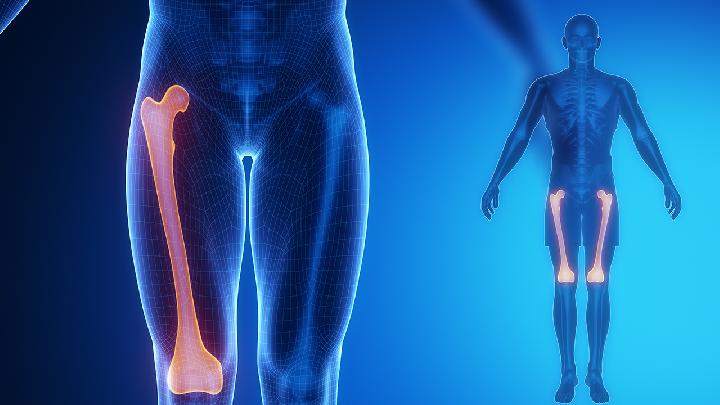

股骨头坏死

股骨头坏死形成的几种原因